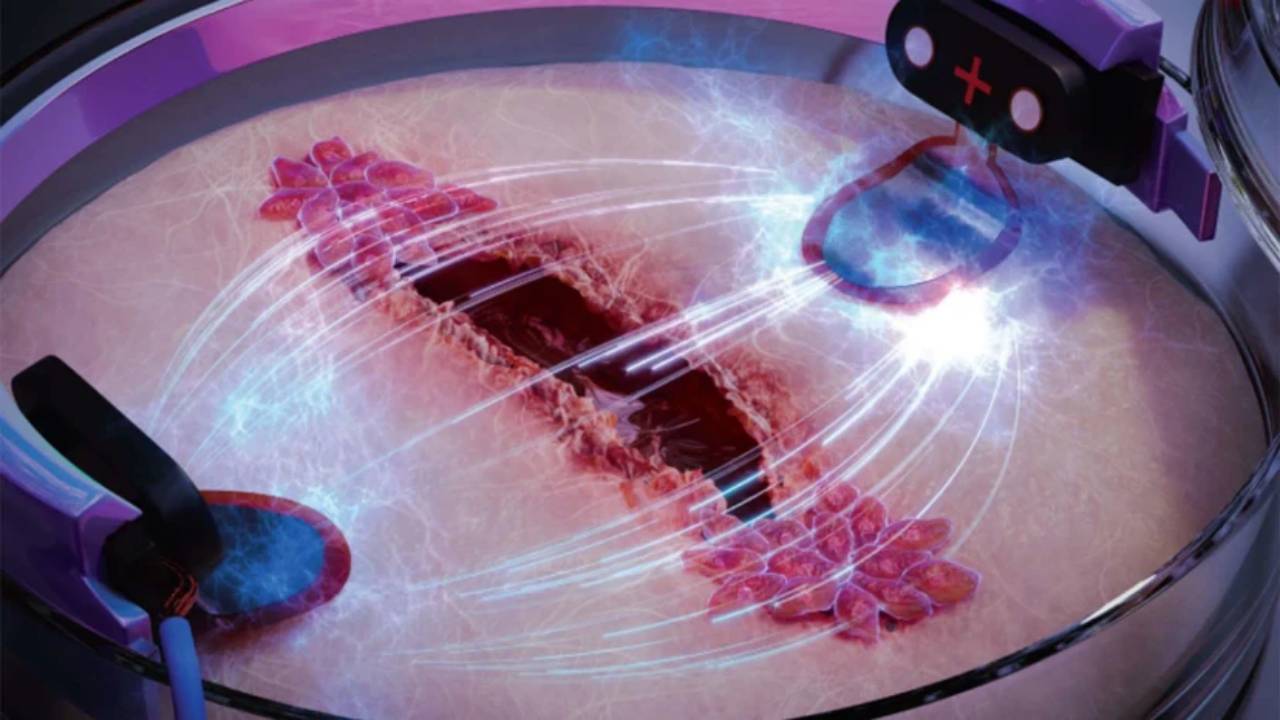

Diagrama que muestra los detalles del experimento de detección de cáncer de pulmón. Crédito: Sociedad Respiratoria Europea / Benoit Audelan.